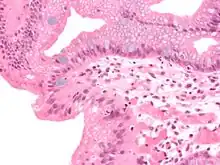

Micrograph of Barrett's esophagus (left of image) and normal stratified squamous epithelium (right of image). Alcian blue stain.

Micrograph of Barrett's esophagus, an example of glandular metaplasia.